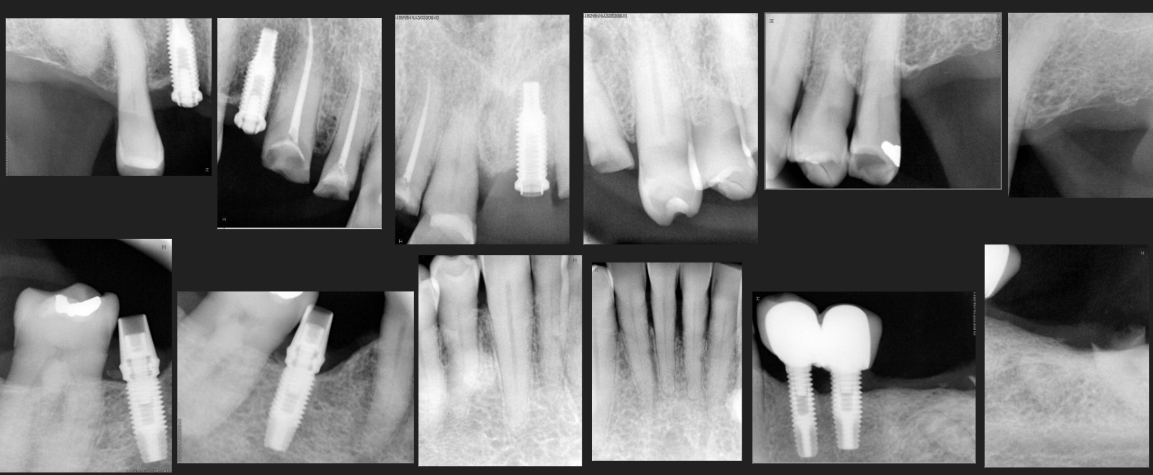

DIAGNÓSTICO: Presenta riesgo y actividad de caries, periodontitis estadío II grado A generalizada, brechas desdentadas clase III del sector I y II (de 15-17 y de 25-27) y sector III (de 35 a 37).

TERAPIA: Terapia básica, complementaria y mantenimiento.